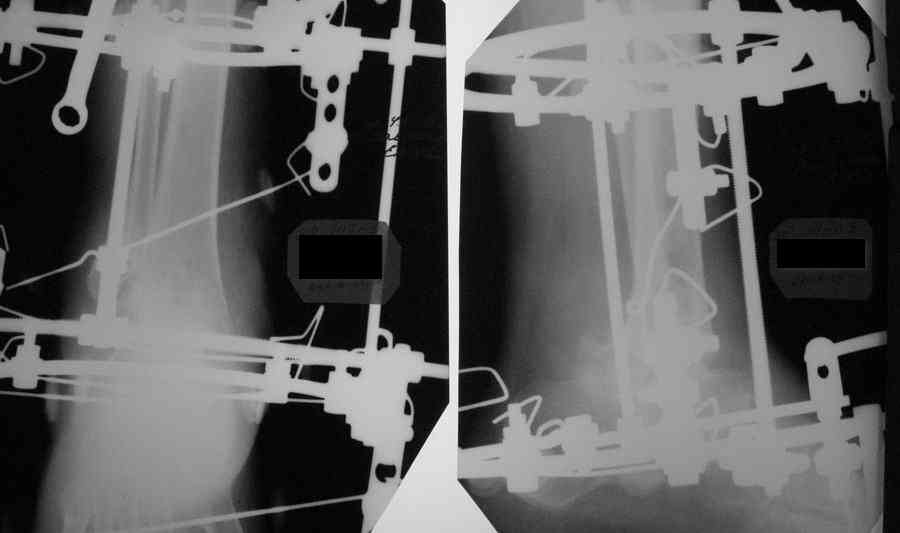

Александр Николаевич! Постарался переделать рентгенограмму - не знаю лучше ли стало- снимки никудышные:(

Стало разборчивее, хотя компрессию картинки можно было еще увеличить.

Смещение стопы кзади видно более отчетливо. Это намеренно так сделано, поскольку так сформировались контактные поверхности?

Погрешности мелкие, на исход лечения вряд ли повлияют. Но все же. По-моему не одинаковые кольца, не корректно введенный согнутый стержень Шанца, проксимальные чрескостные элементы расположены на одной опоре (база на голени вполне могла бы быть из двух колец) и совсем мелкие замечания - грубо загнутые не скушенные концы спиц, местами не отмытая скорее всего с момента операции с конечности и аппарата кровь.